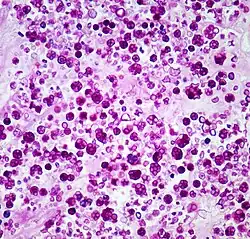

| Histologic stain of a Prototheca zopfii infection in a dog | |

Protothecosis, otherwise known as Algaemia, is a disease found in dogs, cats, cattle, and humans caused by a type of green alga known as Prototheca that lacks chlorophyll and enters the human or animal bloodstream. It and its close relative Helicosporidium are unusual in that they are actually green algae that have become parasites.[1] The two most common species are Prototheca wickerhamii and Prototheca zopfii. Both are known to cause disease in dogs, while most human cases are caused by P. wickerhami.[2] Prototheca is found worldwide in sewage and soil. Infection is rare despite high exposure, and can be related to a defective immune system.[3] In dogs, females and Collies are most commonly affected.[4]

Prototheca has been thought to be a mutant of Chlorella, a type of single-celled green alga. However, while Chlorella contains galactose and galactosamine in the cell wall, Prototheca lacks these. Also, Chlorella obtains its energy through photosynthesis, while Prototheca is saprotrophic, feeding on dead and decaying organic matter. When Prototheca was first isolated from slime flux of trees in 1894, it was thought to be a type of fungus.[6] Its size varies from 2 to 15 micrometres.[7]